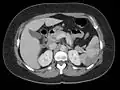

Thrombus of the left ventricle resulting in embolism of the spleen[9]